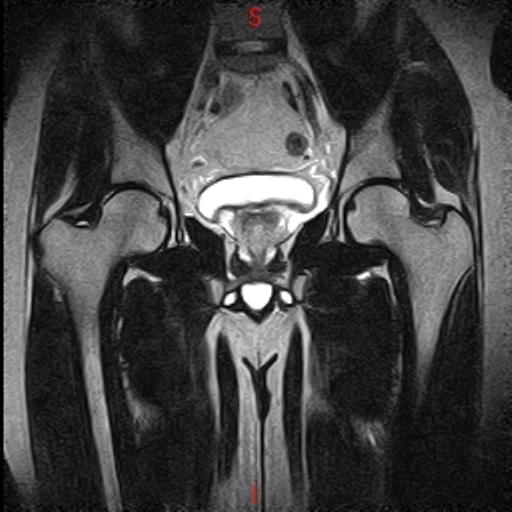

• RESONANCIA NORMAL CADERAS T2 CORONAL

• RESONANCIA NORMAL CADERAS T1 CORONAL